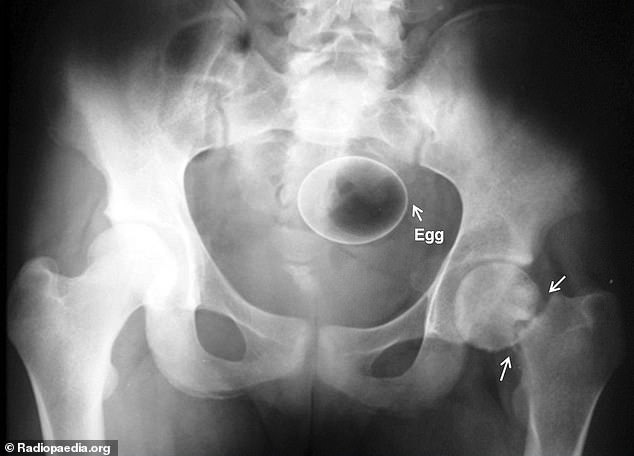

▼塞了一顆蛋!到底…?